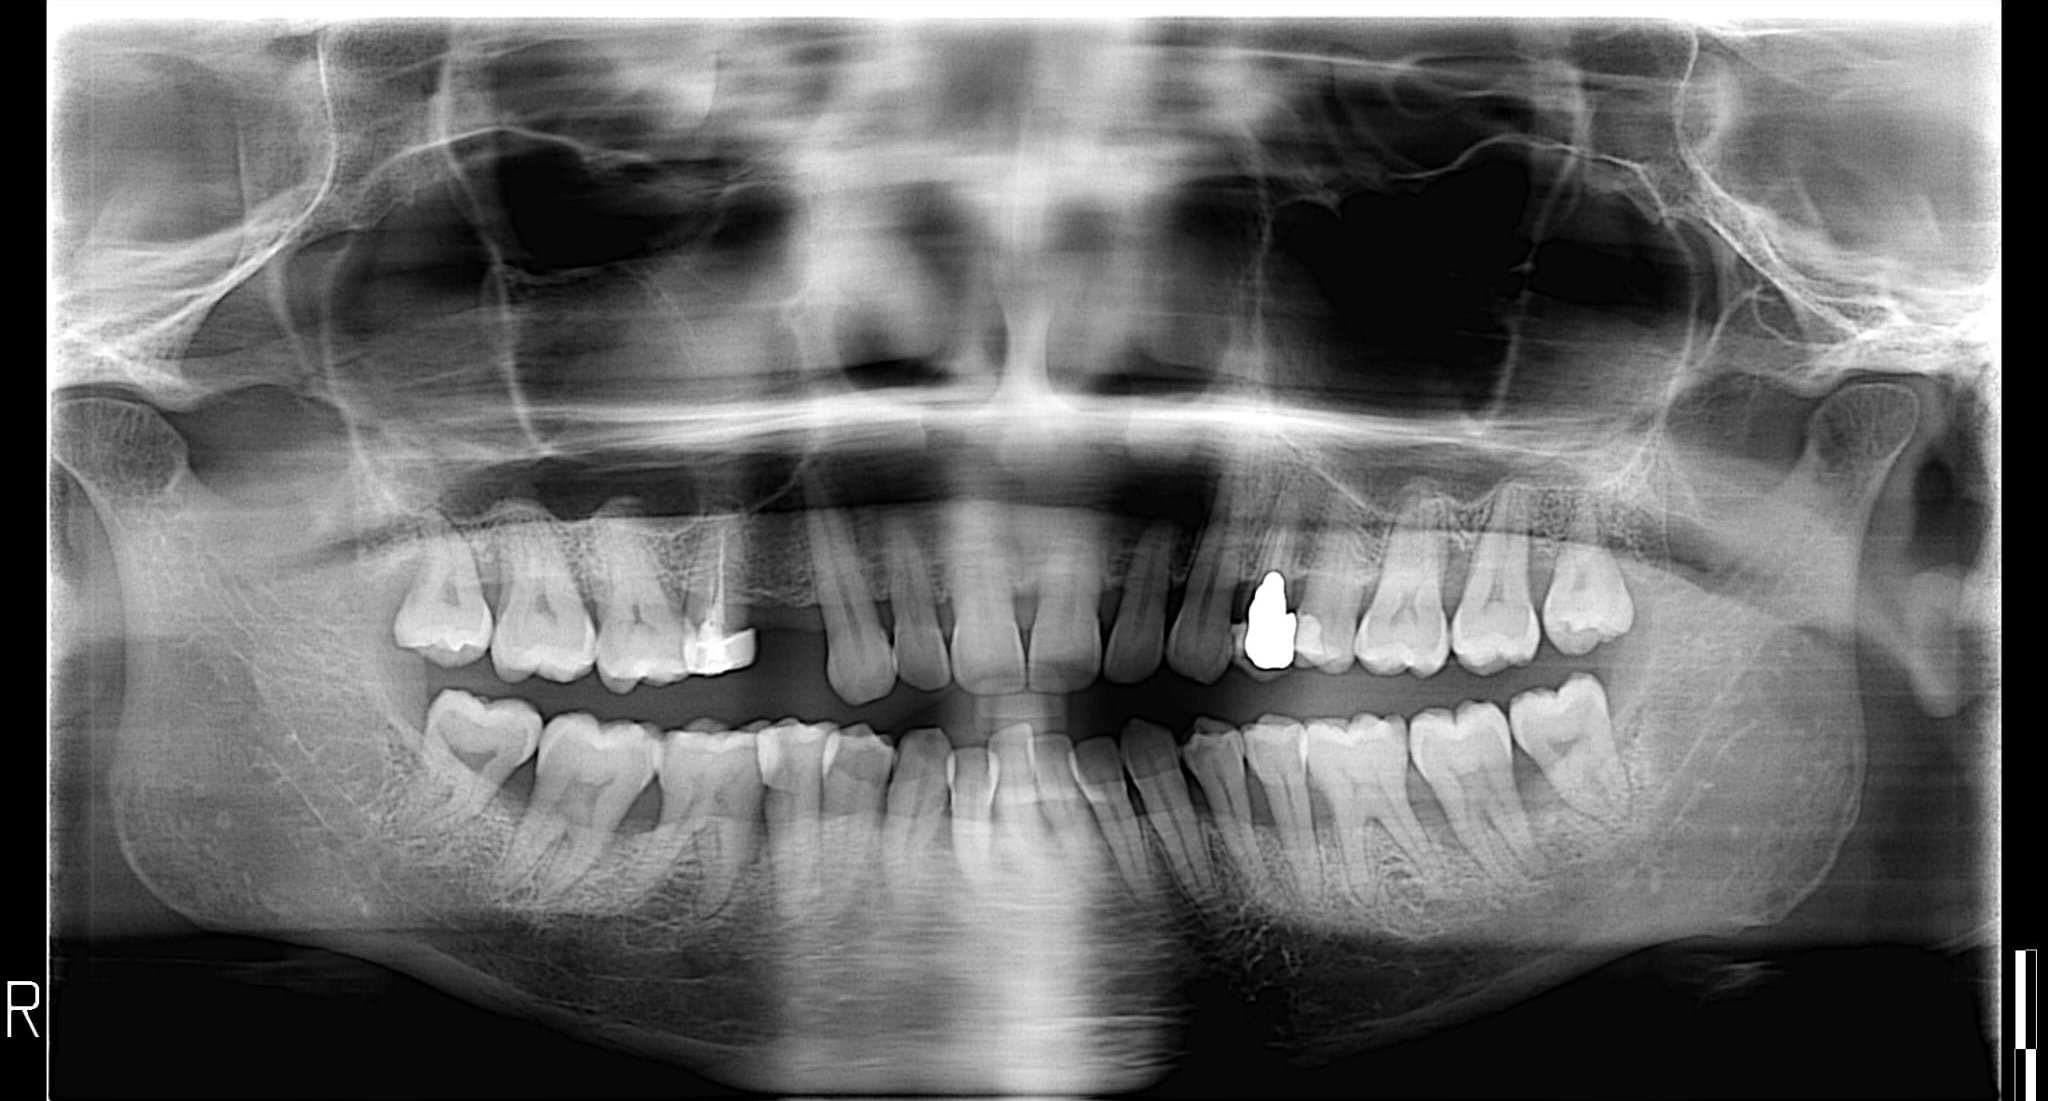

Nel mio caso è necessario rimuovere i denti del giudizio?

Buongiorno, ho 33 anni e ho iniziato a visitare alcuni studi dentistici per valutare l'eventuale utilizzo di un apparecchio invisibile. Per ora ne ho visitati soltanto due ma ho in programma di visitarne altri. La mia domanda è, visti anche i pareri contrastanti degli studi che ho visitato, nel mio caso è necessario (allego